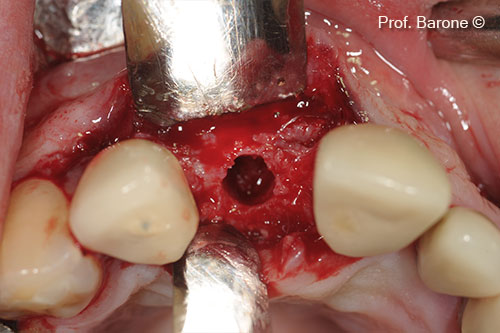

Chuẩn bị vị trí cấy ghép

Cấy ghép implant vào sống hàm đã được tăng cường